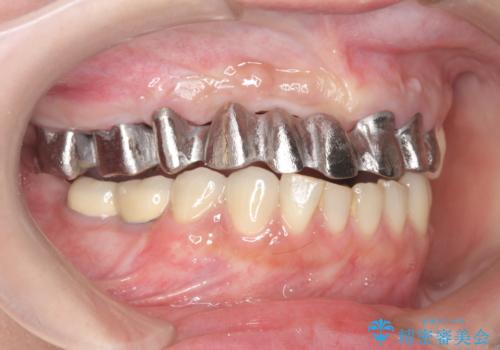

保存の難しい歯の抜歯、保存できる歯の歯周病治療、欠損部位の歯槽堤形態回復を含めブリッジによる安定した咬合機能回復を計画します。

- 90万円 (仮歯×9 メタルボンドクラウン×9)費用は治療当時の料金となります

ブリッジは欠損した部位に臨在する歯を削り、被せなければいけないというデメリットがありますが反面噛む力が強い場合連結することで強大な咬合力に対抗できるというメリットも存在します。